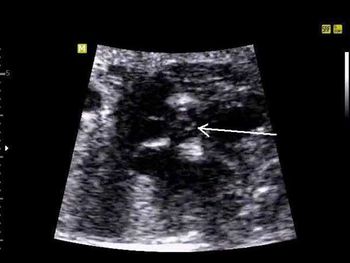

Challenge your diagnostic skills: Can you identify this cardiac defect?